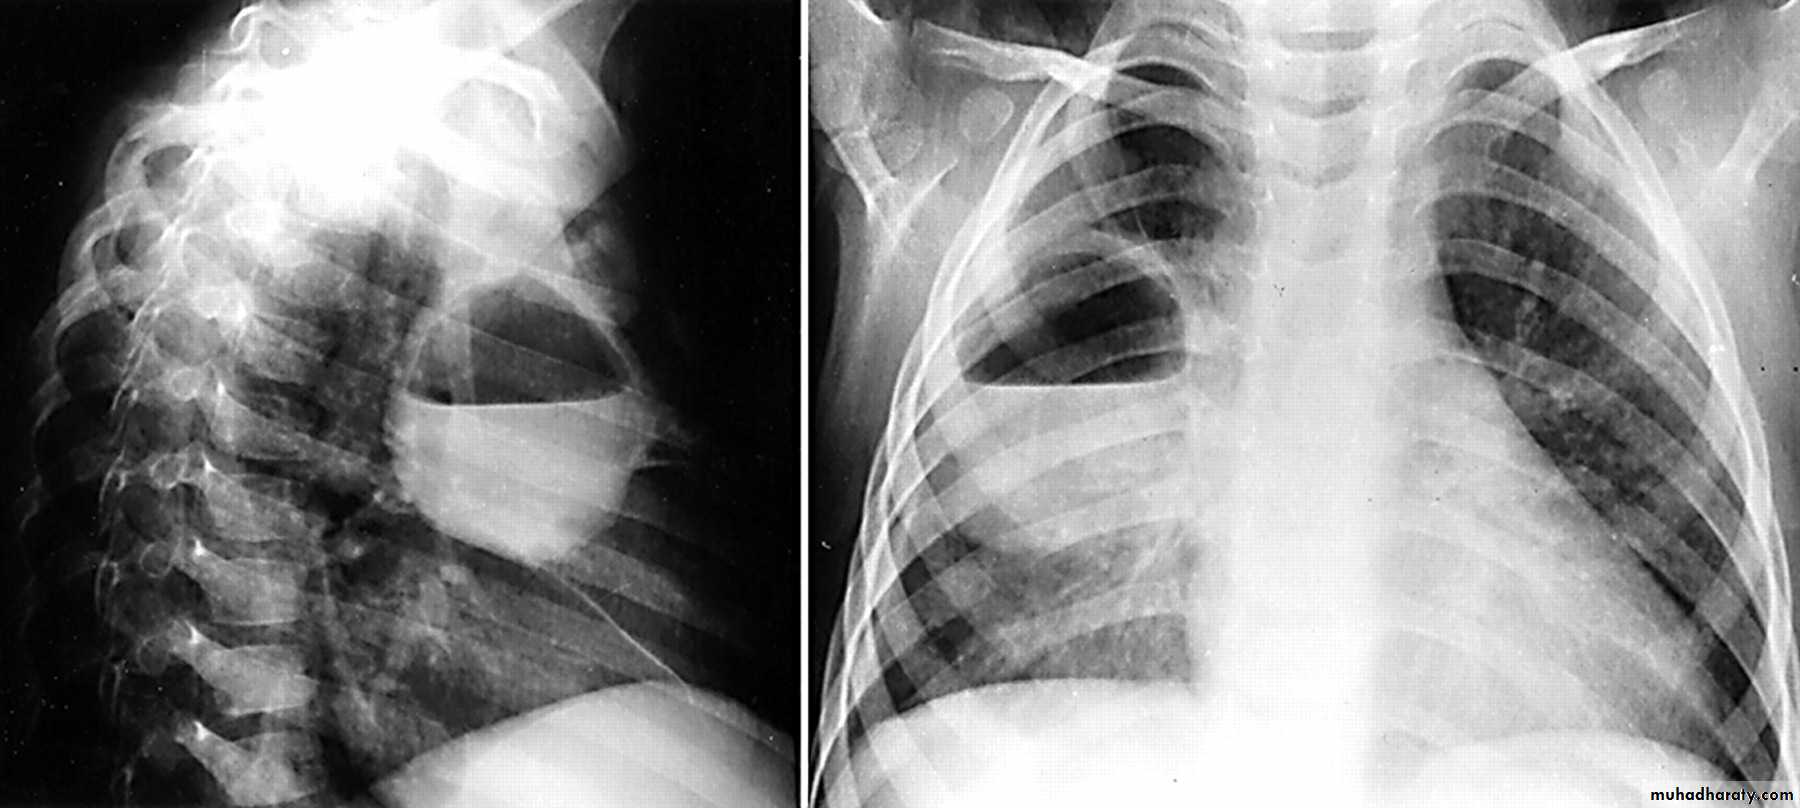

Q ???? Be careful in description & DxBoth of them have similar appearance of broncho pneumonic shadow

??????What is being the pit fall in such films ???

Who can you differentiate ???

Answer the Q in the KEY

After discussion with the students& get their ideas about each films .

62.Q??? Film

63.Q assessment

64.answer this film of Broncho pneumonic (lobular pneumonia ) VS upper zone apical Broncho pneumonic shadow due to post primary TB